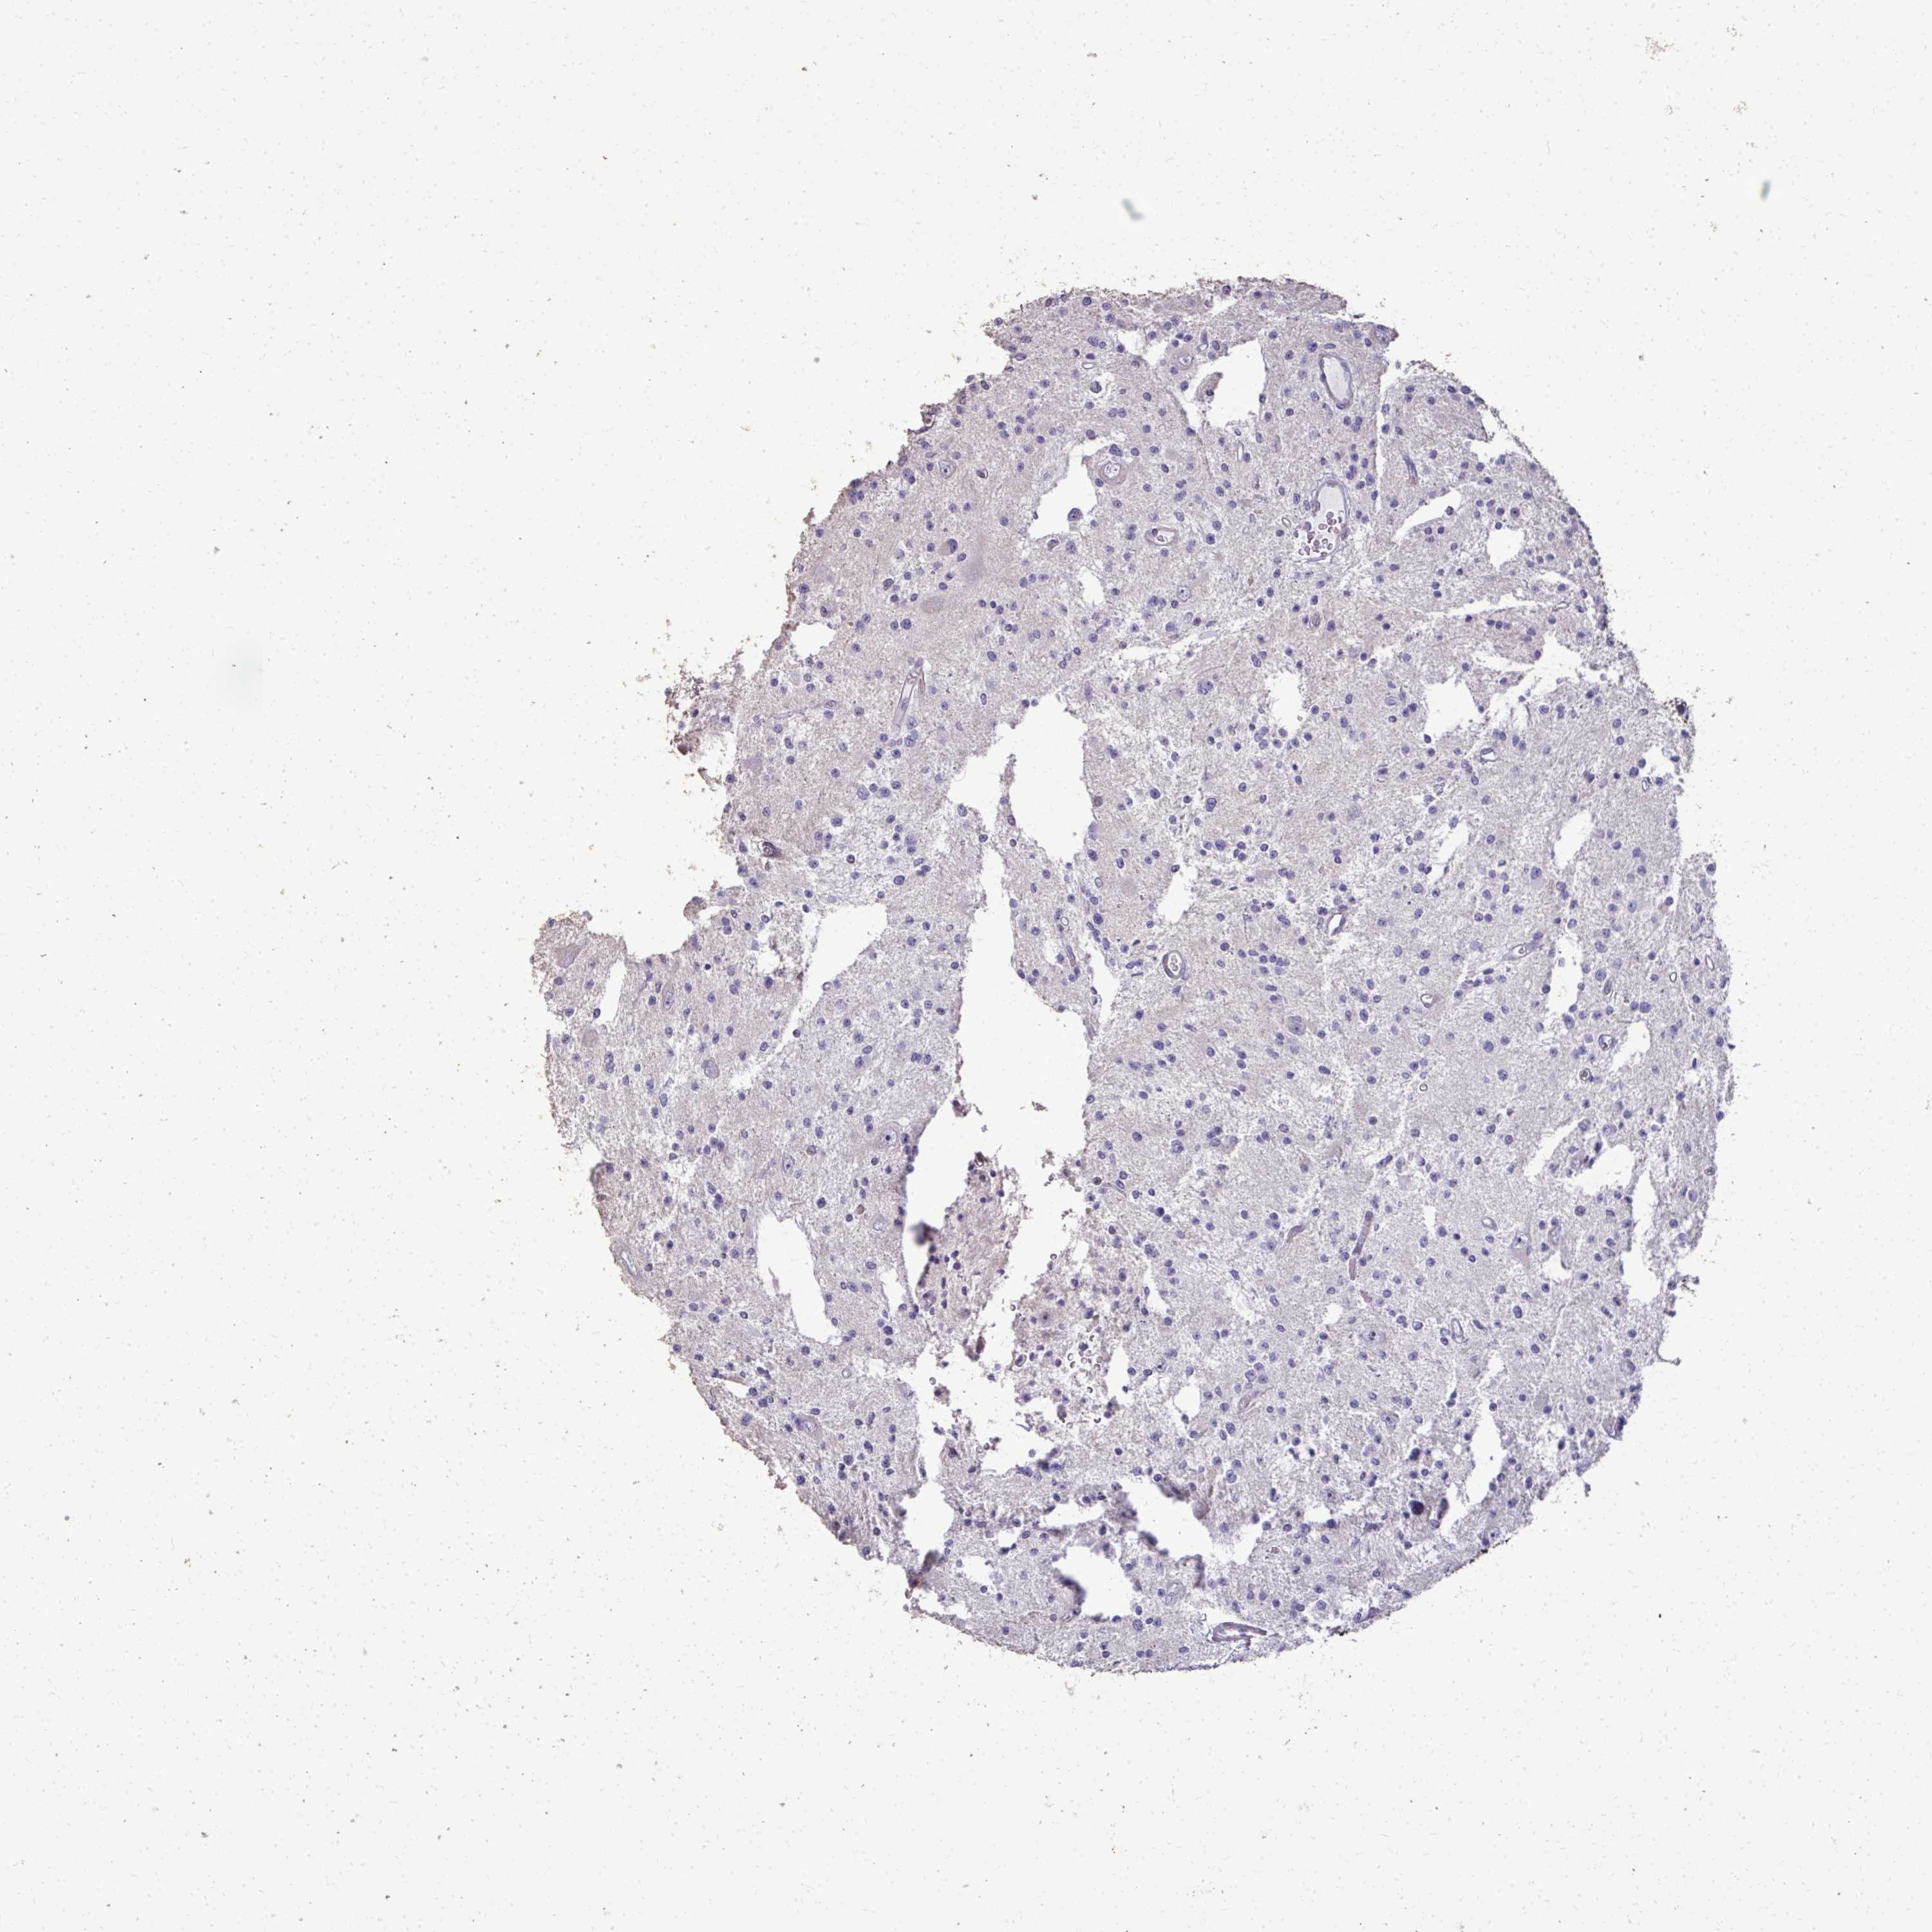

GLIOMA - Protein expressioni

A mouse-over function shows sample information and annotation data. Click on an image to view it in a full screen mode. Samples can be filtered based on level of antibody staining by selecting one or several of the following categories: high, medium, low and not detected. The assay and annotation is described here.

Note that samples used for immunohistochemistry by the Human Protein Atlas do not correspond to samples in the TCGA dataset.

Antibody stainingi

Antibody staining in the annotated cell types in the current human tissue is reported as not detected, low, medium, or high, based on conventional immunohistochemistry profiling in selected tissues. This score is based on the combination of the staining intensity and fraction of stained cells.

Each image is clickable and will lead to virtual microscopy that enables deeper exploration of all samples and also displays staining intensity scores, fraction scores and subcellular localization as well as patient and tissue information for each sample.

Antibody HPA055353

Staining

High

Medium

Low

Not detected

Intensity

Strong

Moderate

Weak

Negative

Quantity

>75%

75%-25%

<25%

None

Location

Nuclear

Cytoplasmic/membranous

Cytoplasmic/membranous,nuclear

Glioma, malignant, Low grade

Glioma, malignant, High grade